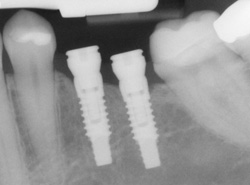

- Multiple-Tooth Implants – Restores several missing teeth in a row with an implant-supported bridge.

- Computer-Enhanced Treatment Planning – 3D imaging allows us to place implants with exceptional precision and predictability.

- Consultation & 3D Imaging – We review your oral health and bone density using advanced imaging.